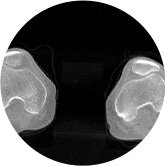

智能金属伪影抑制算法

关闭金属伪影校正

开启金属伪影校正